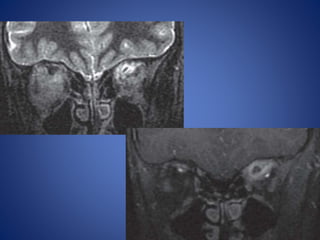

Retinal detachment

Choroidal detachment

Choroidal detachment is accumulation of blood or fluid in supra

choroidal space between choroid and sclera, so collection extend

circumferentially along the entire supra choroidal space ,

configuration is lentiform shaped along medial as well as lateral wall

of globe, choroid bulging medially on either side giving so called

kissing choroid sign.

Anteriorly extend upto ciliary bodies and posterior limit formed by

anchoring effect of short posterior ciliary arteries and nerves

preventing convergence of detached choroidal leaves to a single

point.

Configuration of collectionis cresent shaped or V shaped on axial sections. Limbs of V represent detached leaves of retina converging towards optic disc represent the apex of V. Collection anteriorly extend upto ora serrata represent anterior limit due to normal anterior attachment of retina. Retinal detachment

Choroidal detachment Choroidal detachmentis accumulation of blood or fluid in supra choroidal space between choroid and sclera, so collection extend circumferentially along the entire supra choroidal space , configuration is lentiform shaped along medial as well as lateral wall of globe, choroid bulging medially on either side giving so called kissing choroid sign. Anteriorly extend upto ciliary bodies and posterior limit formed by anchoring effect of short posterior ciliary arteries and nerves preventing convergence of detached choroidal leaves to a single point.